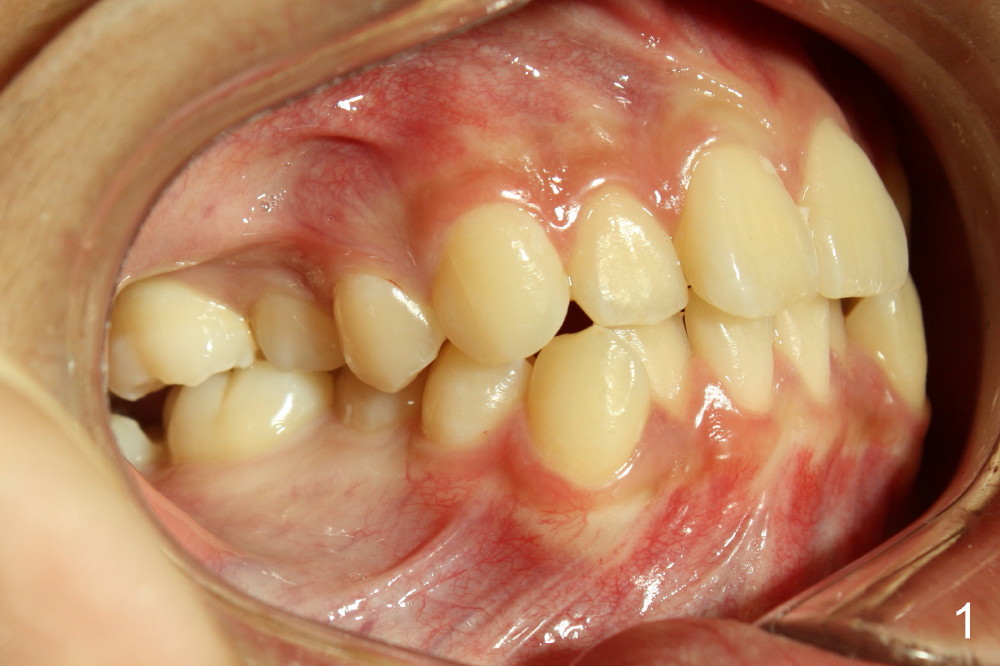

A 13-year-old boy has severe crowding (Fig.1-5). Four of the first bicuspids were extracted on 02/17/2014. Full mouth brackets or bands (except #18) were placed on 03/27/2014. Alignment improved 2 months later (Fig.11, 05/24/2014). The upper 18 ss wire was modified (Fig.12), and fixed with alastiks (Fig.13,14). One month later (07/01/2014), local alignment also improved (Fig.15); the upper modification is confined to one tooth.